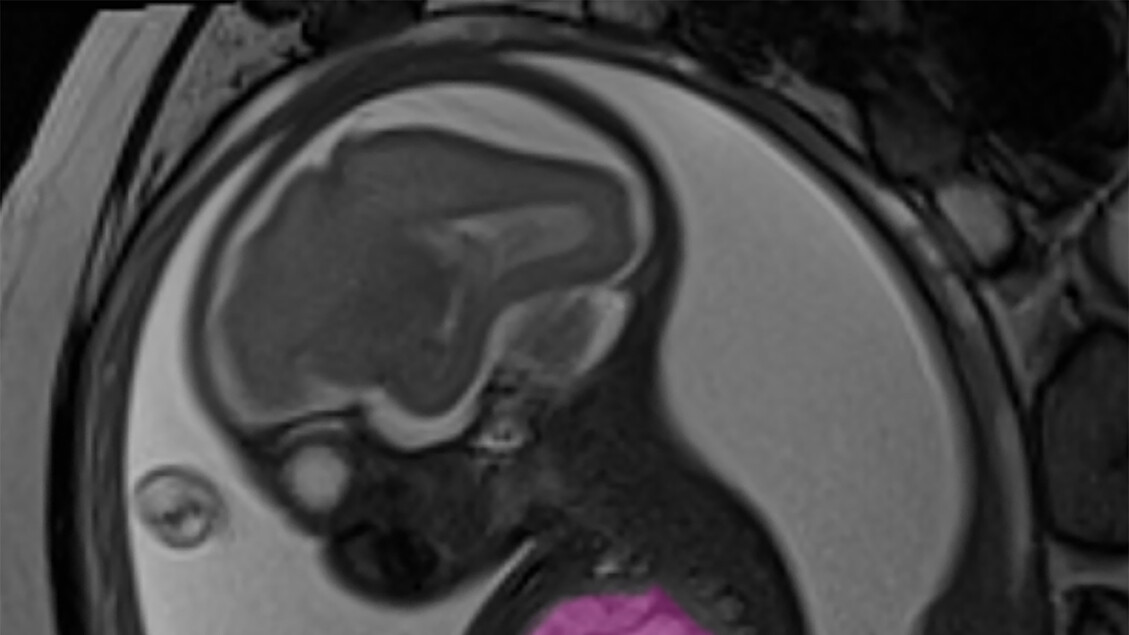

Un caso straordinario di **medicina fetale** ha avuto luogo a **Roma**, dove un **neonato** è stato salvato grazie a un **intervento chirurgico** eseguito mentre si trovava ancora nel **grembo materno**. Il protagonista di questa storia è **Alessandro** (nome di fantasia), un **bambino** che ha affrontato una **sfida significativa** a causa di una **cisti polmonare** di dimensioni notevoli, grande quanto un’arancia, che metteva in pericolo la sua vita. La **madre**, una donna di 35 anni, si trovava alla 24esima settimana di **gravidanza** quando è stata effettuata la **diagnosi** di questa **condizione critica**.

L’intervento chirurgico è stato eseguito dall’équipe di **chirurgia fetale** dell’**ospedale pediatrico Bambino Gesù** di **Roma**. La **cisti**, che misurava circa 9x6x5 centimetri, stava comprimendo il **cuore** e i **polmoni** del **feto**, causando uno **scompenso cardiaco** che avrebbe potuto portare a conseguenze fatali. Per affrontare questa situazione, i **chirurghi** hanno posizionato uno **shunt pleuro-amniotico**, un dispositivo che consente la comunicazione tra il **torace** del **feto** e il **liquido amniotico**, ripristinando così la normale **funzionalità cardiaca**.

Il **dottor Andrea Conforti**, responsabile dell’unità di **chirurgia fetale** e **neonatale** del **Bambino Gesù**, ha commentato l’importanza dell’intervento, sottolineando che la **cisti** occupava quasi tutto il **torace** del piccolo. Nonostante ora **Alessandro** respiri con due **lobi polmonari** anziché tre, i lobi rimasti si sono espansi e compensano perfettamente la **funzione respiratoria**. Ciò gli consentirà di avere una **vita normale** e di praticare **sport** in futuro.